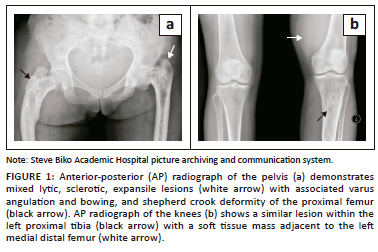

A 54-year-old woman presented to the orthopaedic tumour clinic at our institution with a history of a slow-growing, painful, soft tissue mass in the distal left thigh. The patient was admitted for further work-up. The biochemical studies were normal. Radiographs of the pelvis (Figure 1a) demonstrated expansile, mixed lytic and sclerotic lesions of both proximal femora with an associated shepherd crook deformity of the right femur and cranial migration of the left femur. Radiographs of the knees (Figure 1b) showed a mixed lytic-sclerotic lesion of the left proximal tibia with an impression of a soft tissue mass adjacent to the medial distal femur. The bony findings were in keeping with polyostotic FD.